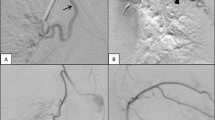

The mechanisms of recurrent haemoptysis are shown in Fig. 2 and Table 2. In general, recanalisation (45.2%) of HRAs was the most common cause in patients with recurrent haemoptysis, followed by new HRA (38.5%), bridging collaterals (14.7%) and conventional collaterals (1.7%) (Fig. 2A). We have presented representative cases with recanalisation and bridging collaterals in Fig. 3 for reference. In a retrospective review of all new HRAs, four could be identified using e-CT evaluation at the 1st series ssBACE. The new HRA category includes the vessels that were overlooked (n = 4) or ones that could not be embolised (n = 3) at the time of the 1st series ssBACE. Several subsets of patients, such as those with no exacerbation of underlying disease (Fig. 2B) and those receiving an anticoagulant (Fig. 2C) or antiplatelet agent (Fig. 2D), showed statistically significant different trends.

Representative cases of recanalisation and bridging collateral after ssBACE. Representative cineangiography findings of recanalisation (a–d) and bridging collateral (e–h) after 1st series ssBACE. Cineangiography revealed a dilated tortuous left bronchial (a) and right 7th ICA (e) with a bronchopulmonary shunt, which were embolised using metallic coil deployment during 1st series ssBACE (b and f; white arrows). For the treatment of recurrent haemoptysis, the patient underwent 2nd series ssBACE where cineangiography demonstrated a recanalisation (c; yellow arrows) or bridging collateral (g; yellow arrows) of the first embolised part of the HRA. Second series ssBACE was performed successfully at the proximal site of these HRAs (d and h; white arrows). ICA intercostal artery, HRA haemoptysis-related artery, ssBACE super-selective bronchial artery coil embolisation